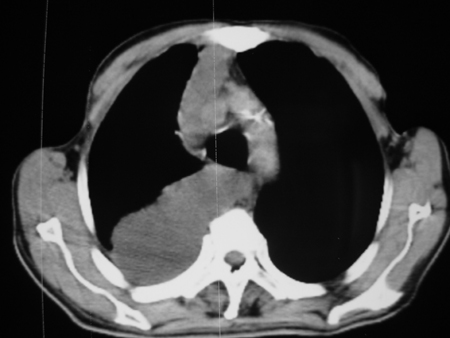

男77岁,胸痛就诊

右侧胸腔积液,部分包裹,右下肺膨胀不全,右下肺感染。

考虑右肺门占位并下叶不张 右胸包裹积液

右侧胸腔积液,部分包裹,右下肺膨胀不全